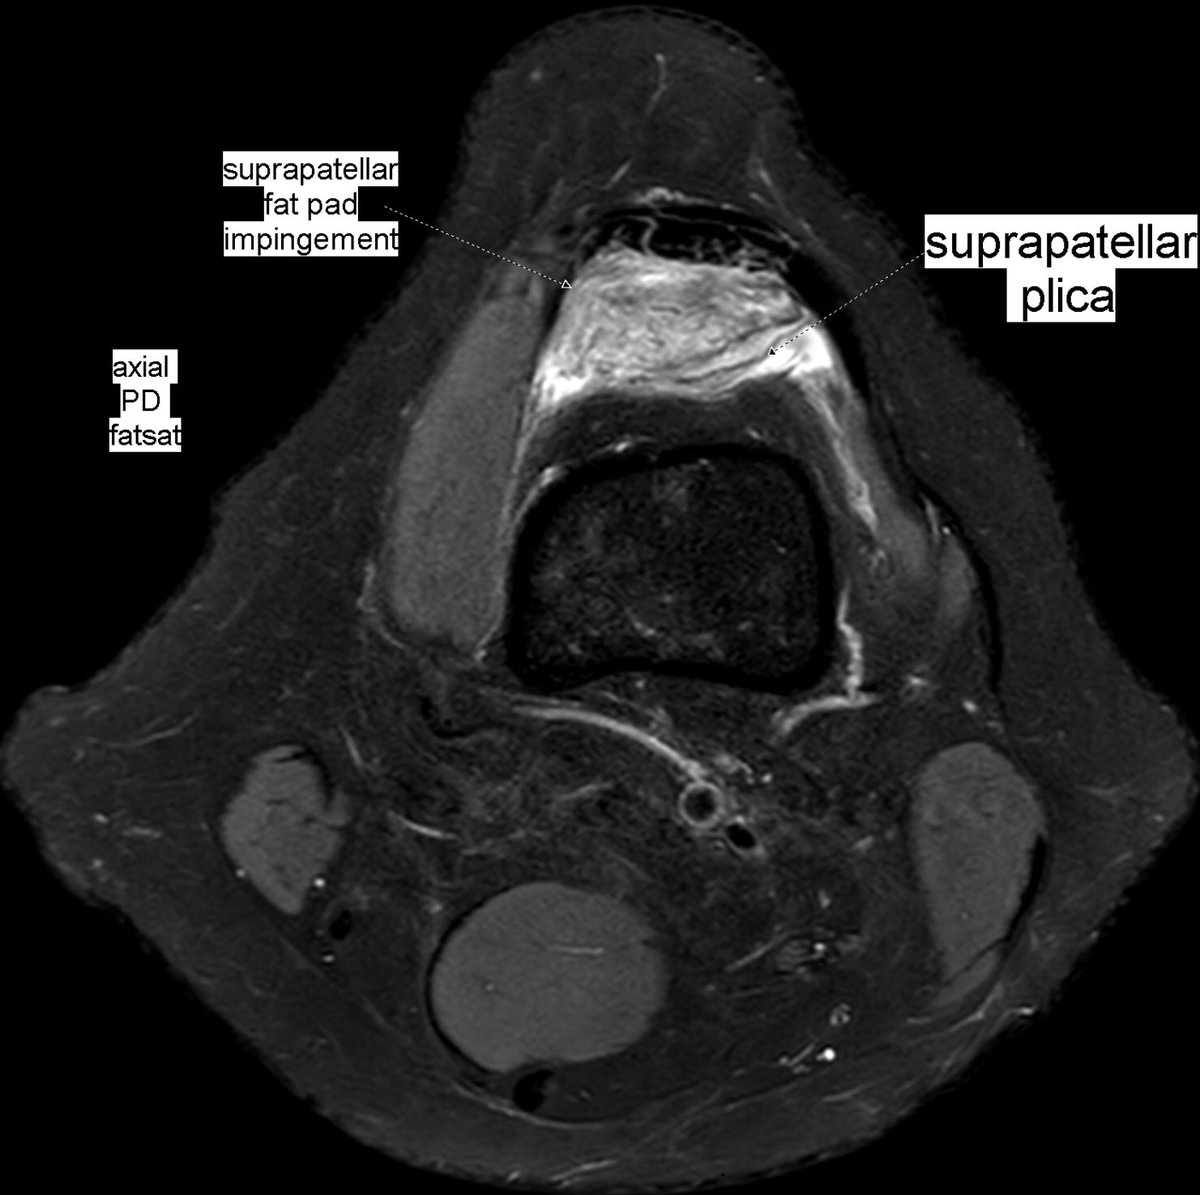

Patient with anterior knee pain. Localized synovitis of suprapatellar recess and suprapatellar fat pad impingement syndrome secondary to a suprapatellar plica: suprapatellar plica syndrome.

#MSKrad#knee#orthopaedics#radiology https://www.ncbi.nlm.nih.gov/pmc/articles/PMC6477514/pdf/main.pdf …pic.twitter.com/fvk7MUuDNt